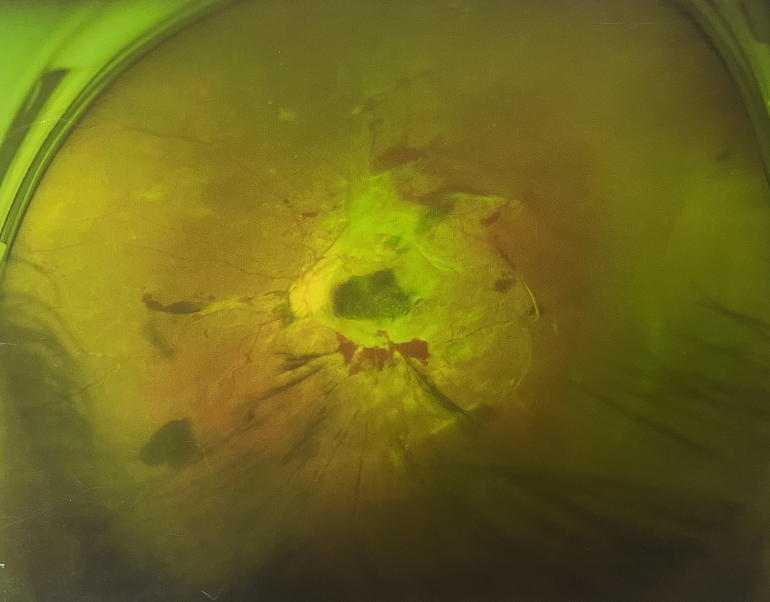

4個(gè)月前的左眼

左眼發(fā)展到糖尿病視網(wǎng)膜病變VI期

由于王女士的左眼沒有聽從醫(yī)生盡快做手術(shù)的建議,一直耽誤,從4月前的0.4視力逐漸下降到僅剩眼前手動,導(dǎo)致左眼發(fā)展到糖尿病視網(wǎng)膜病變VI期(屬于6期糖網(wǎng)中的晚期),已經(jīng)產(chǎn)生大量新生血管+纖維增值+廣泛牽拉性視網(wǎng)膜脫離,由于耽誤了病情,且病情發(fā)展異常迅速,導(dǎo)致目前左眼連保住眼球都很困難。

“而如果4月余前,左眼及時(shí)手術(shù)(當(dāng)時(shí)左眼病情比右眼輕,增殖膜還未累及黃斑),左眼將恢復(fù)的比右眼還好,甚至可以恢復(fù)到0.8或1.0,而現(xiàn)在連保住眼球的機(jī)會都很渺茫”,張小虎醫(yī)生表示實(shí)在可惜。